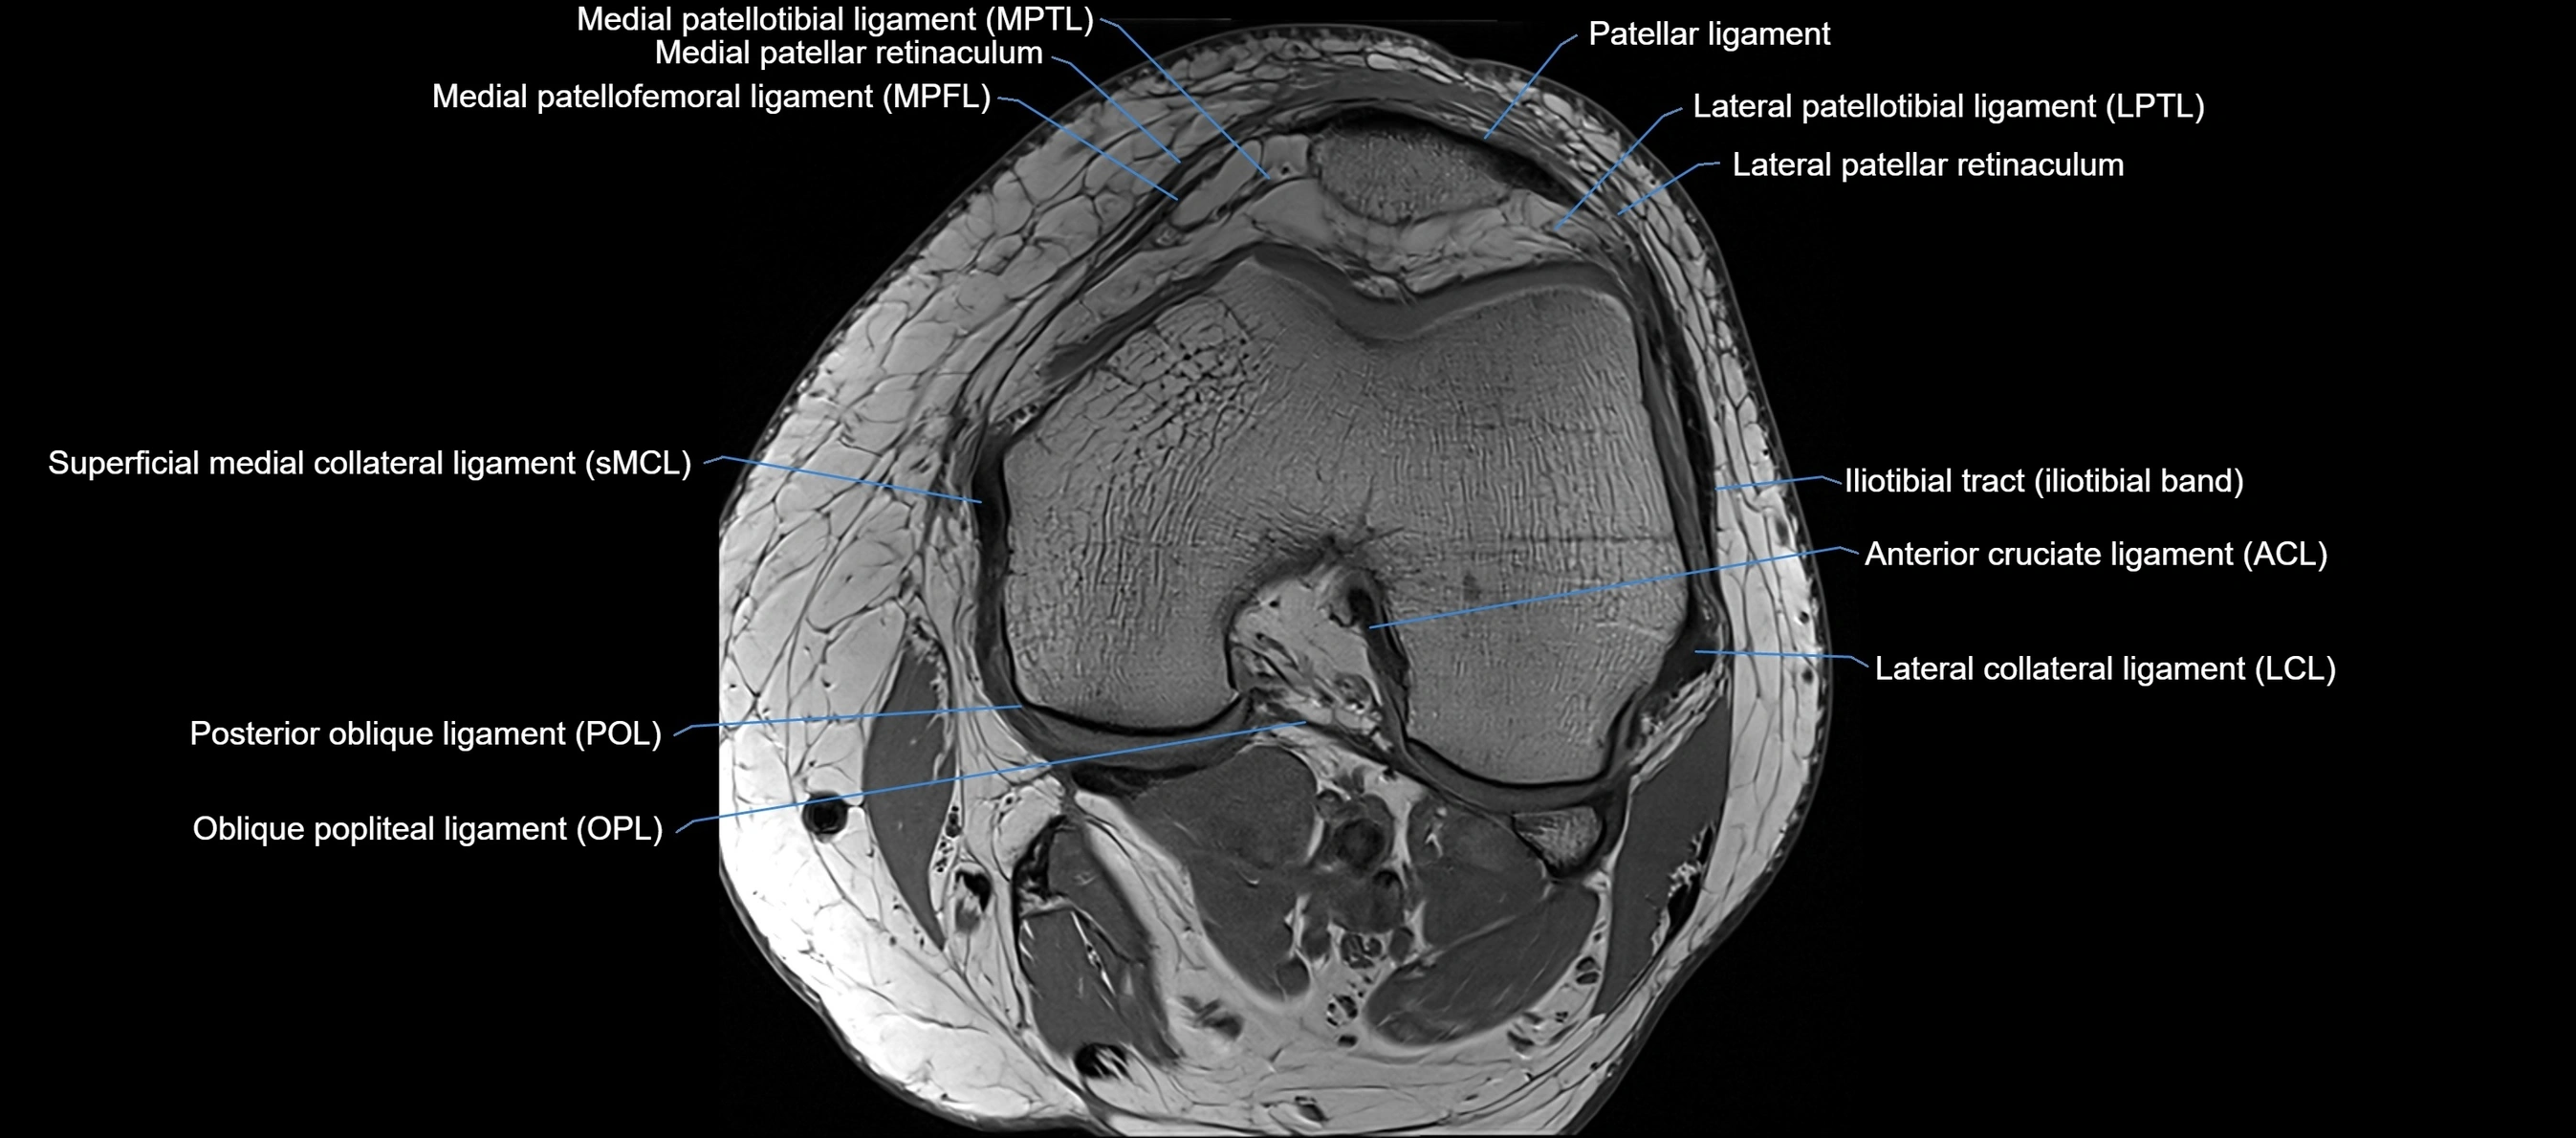

MRI Appearance

T1-weighted images:

• Normal ACL appears as a low-signal band-like structure crossing the intercondylar notch

• Surrounded by intermediate signal synovial fluid and fat planes

T2-weighted images:

• Normal ACL remains low signal

• Partial or complete tears appear as discontinuity, increased signal, or fiber laxity

MRI images

image